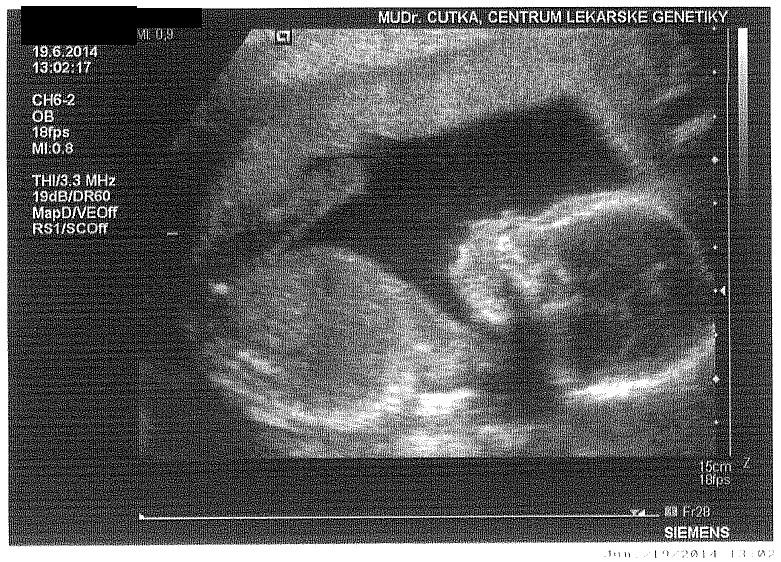

@nynus já jsem kvůli nespokojenoti s minulou DR, změnila a teď chodím k DR. do Písku do nemocnice. Ona pracuje i v Budějcích v Artu (CAR) a je naprosto dokonalá-mladá, necpe do hlavy žádné blbosti a hodně se vyzná v problémech s otěhotněním... A zná se s Čutkou mladším i starším, takže tam jsem jako prominentní pacoš 🙂

jojojjo si z budejc Dr.Cutka znam ho 🙂 ale mam Dr. Lisku,no ted sem teda v UK